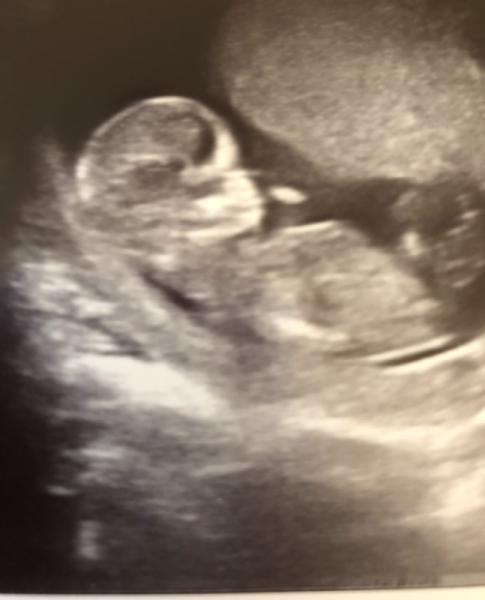

Geht mir genauo, ich bin auch seit Montag im 4. Monat:)

Bild zu